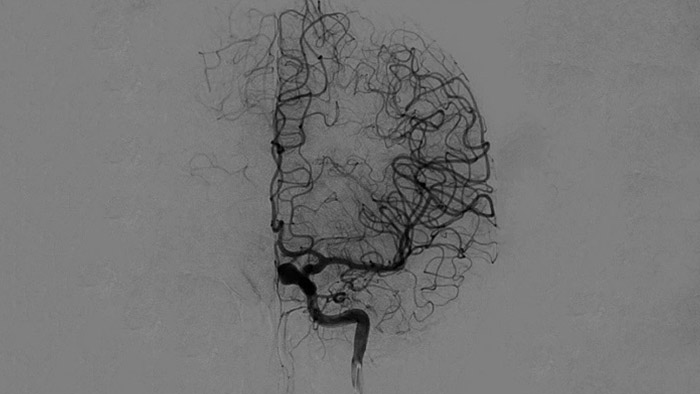

Imágenes nítidas con angiografía de sustracción digital (DSA) 2D con tecnología ClarityIQ

DSA 2D con tecnología ClarityIQ

ClarityIQ aplica la compensación automática del movimiento durante la angiografía de sustracción digital (DSA) en tiempo real para mantener imágenes nítidas de los vasos. Esto respalda la toma de decisiones fundamentadas durante los procedimientos de accidente cerebrovascular.

Confirme el éxito del tratamiento

Visualización DSA

Las visualizaciones de DSA de alta calidad le permiten evaluar si ha recuperado el coágulo completo y si se han dispersado trozos de coágulo distalmente en el cerebro. Puede verificar la restauración del flujo sanguíneo a la penumbra y verificar si hay hemorragias periprocedimiento.